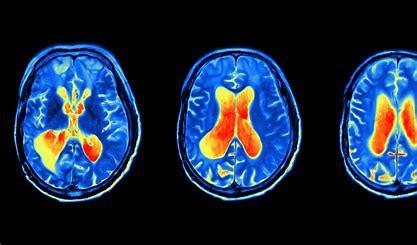

fMRI反映神经活动变化是基于神经血管耦合性(BOLD)的原理,即由于特定味觉刺激,局部脑区的活动会引起周围血氧水平上升,这个变化可以通过fMRI图像反映出来。fMRI成像是全脑成像,空间分辨率高,但时间分辨率不如EEG,所以对fMRI的分析一般是以获得不同味觉刺激下分别被激活的脑区以及各脑区之间活动的网络效应为目的。和EEG不同的是,受试者需要以仰卧位躺在扫描床上,头部放置在包含泡沫垫的头部线圈内,由于fMRI成像过程受试无法大幅度咀嚼,所以刺激物一般为液体。fMRI创建了包括时间和三维空间在内的四维数据,数据的初步分析从两个预处理步骤开始,第一个是重新排列过程,通过数据修正来纠正食物品尝过程中口腔器官运动带来的干扰。第二步是归一化,将重组后得到的脑图像装入模板(由蒙特利尔神经学研究所提供),校正个体不同头部大小和形状的影响。在预处理之后,使用参考刺激来识别第一级分析中活跃的大脑区域,将生成β图,在第二级分析中,感觉信息一般使用单变量或多体素模式分析(MVPA)将预处理后的信号数据与beta图进行比较获得。

通过对fMRI数据的分析,研究人员发现了额叶区和顶盖区的识别能力。另外人们还发现味觉刺激引起的大脑反映有刺激位置的差别,发现在左侧口腔中注射盐溶液会引起左侧大脑集群激活,而右侧注射则不会影响丘脑的反应。另外味觉刺激的强度会引起不同的神经活动特点,通过甜味和苦味刺激,人们发现双侧大脑被激活区域的大小和甜度与苦度呈负相关趋势,这种刺激差异引起的脑区活动特异性变化为味觉反应的研究提供了一定的参考。